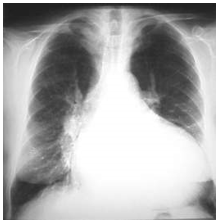

Son asintomáticos en su mayoría. Suelen diagnosticarse por un soplo cardiaco a partir de los 2-3 años, aunque muchos ya son vistos en época neonatal de forma no patológica. Produce sobrecarga de volumen de cavidades derechas (AD y VD) con ligero hiperaflujo pulmonar. A la auscultación, cuando el defecto es moderado-grande suelen ocasionar un soplo sistólico. El ECG puede ser normal o dar datos de crecimiento de ventrículo derecho y la radiografía tórax suele ser normal.

- Formas críticas neonatales: Debut con síntomas de insuficiencia cardiaca. Pulsos débiles en 4 miembros. Cardiomegalia y congestión pulmonar en la radiografía de tórax.

- Formas no neonatales: Asintomáticos. La radiografía de tórax suele ser normal, pudiendo encontrarse ligera dilatación de la aorta ascendente.